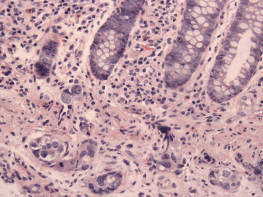

In April 2013, this 60-year-old mother of six children was diagnosed with dermatomyositis, with periungual telangiectasias, malar erythema, fatigue for the previous 6 months, and clinical as well as laboratory signs of muscle inflammation. Her initial treatment consisted of prednisone, and later continued with intermittent dexamethasone, hydroxychloroquine, quinacrine (added in June) and methotrexate (added in October). Additional medical history included chronic urinary complaints related to uterine prolapse since 1994. There was no family history of cancer or autoimmune disease. In November 2013, abdominal discomfort led to a colonoscopy with the finding of a submucosal protuberance in the transverse colon (Figure 1); biopsy was consistent with a poorly differentiated carcinoma and immunohistochemical features of a high-grade serous malignancy of likely gynaecologic origin. Further evaluation by computerised tomography (CT) identified abnormalities confirmed at a subsequent laparotomy in December 2013: diffuse metastases up to 2 cm in liver parenchyma as well as 3 cm mesenteric and retroperitoneal nodes, an omental mass infiltrating the transverse colon, bilateral tubo-ovarian masses and a 2-cm cul-de-sac nodule; adnexectomies and omental biopsies were performed with pathology confirming high-grade serous carcinoma arising from the right and left fallopian tubes (American Joint Commission on Cancer (AJCC) stage pt3bNxM1, Fédération Internationale de Gynécologie et d’Obstétrique (FIGO) stage IV b). She received five cycles of NACT with carboplatin and paclitaxel from January 2014 to April 2014 (Table 1) with excellent tolerance except with her urinary symptoms and pelvic pressure. After normalisation of serum CA125 and CT findings, in May 2014, she underwent an exploratory laparotomy that included negative frozen section of the liver, a completion hysterectomy and absence of tumour in biopsies of the cul-de-sac-omentum, residual right ovary, abominal and vesical wall, coupled with uterosacral ligament suspension, anterior and posterior pelvic floor repair, midurethral synthetic sling, cystoscopy and insertion of an indwelling catheter and IP port. Post-operatively, one IV and two IP doses of 40 mg/m2 cisplatin were given as consolidation with the last treatment taking place in July 2014. Post-treatment CT and removal of the IP port took place later in 2014 when she was asymptomatic. In June 2015, an episode of cutaneous Herpes zoster (shingles) was treated with famcyclovir by her local physician a few days after its onset, with full resolution except for mild post-herpetic neuralgia. Otherwise, she has experienced no symptoms, and continues to have near complete relief of urinary symptoms after her bladder suspension operation. A routine colonoscopy in November 2017 (by the same specialist who diagnosed her transverse colon metastasis) showed an absence of the previous findings, and she remains well 4 months later.

Figure 1. A submucosal protuberance in the transverse colon. Supplied by Dr Pascale Levine.